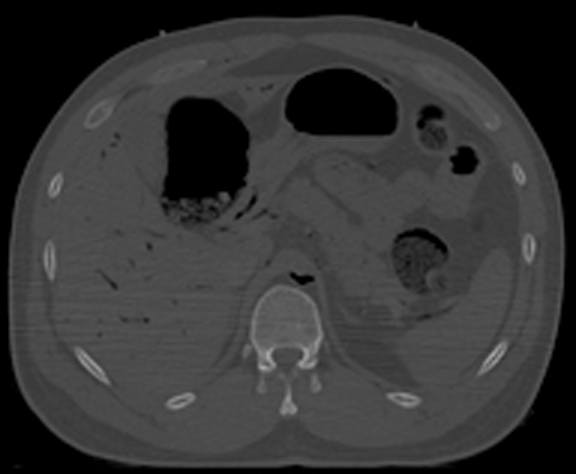

Horizontal CT Section at this level